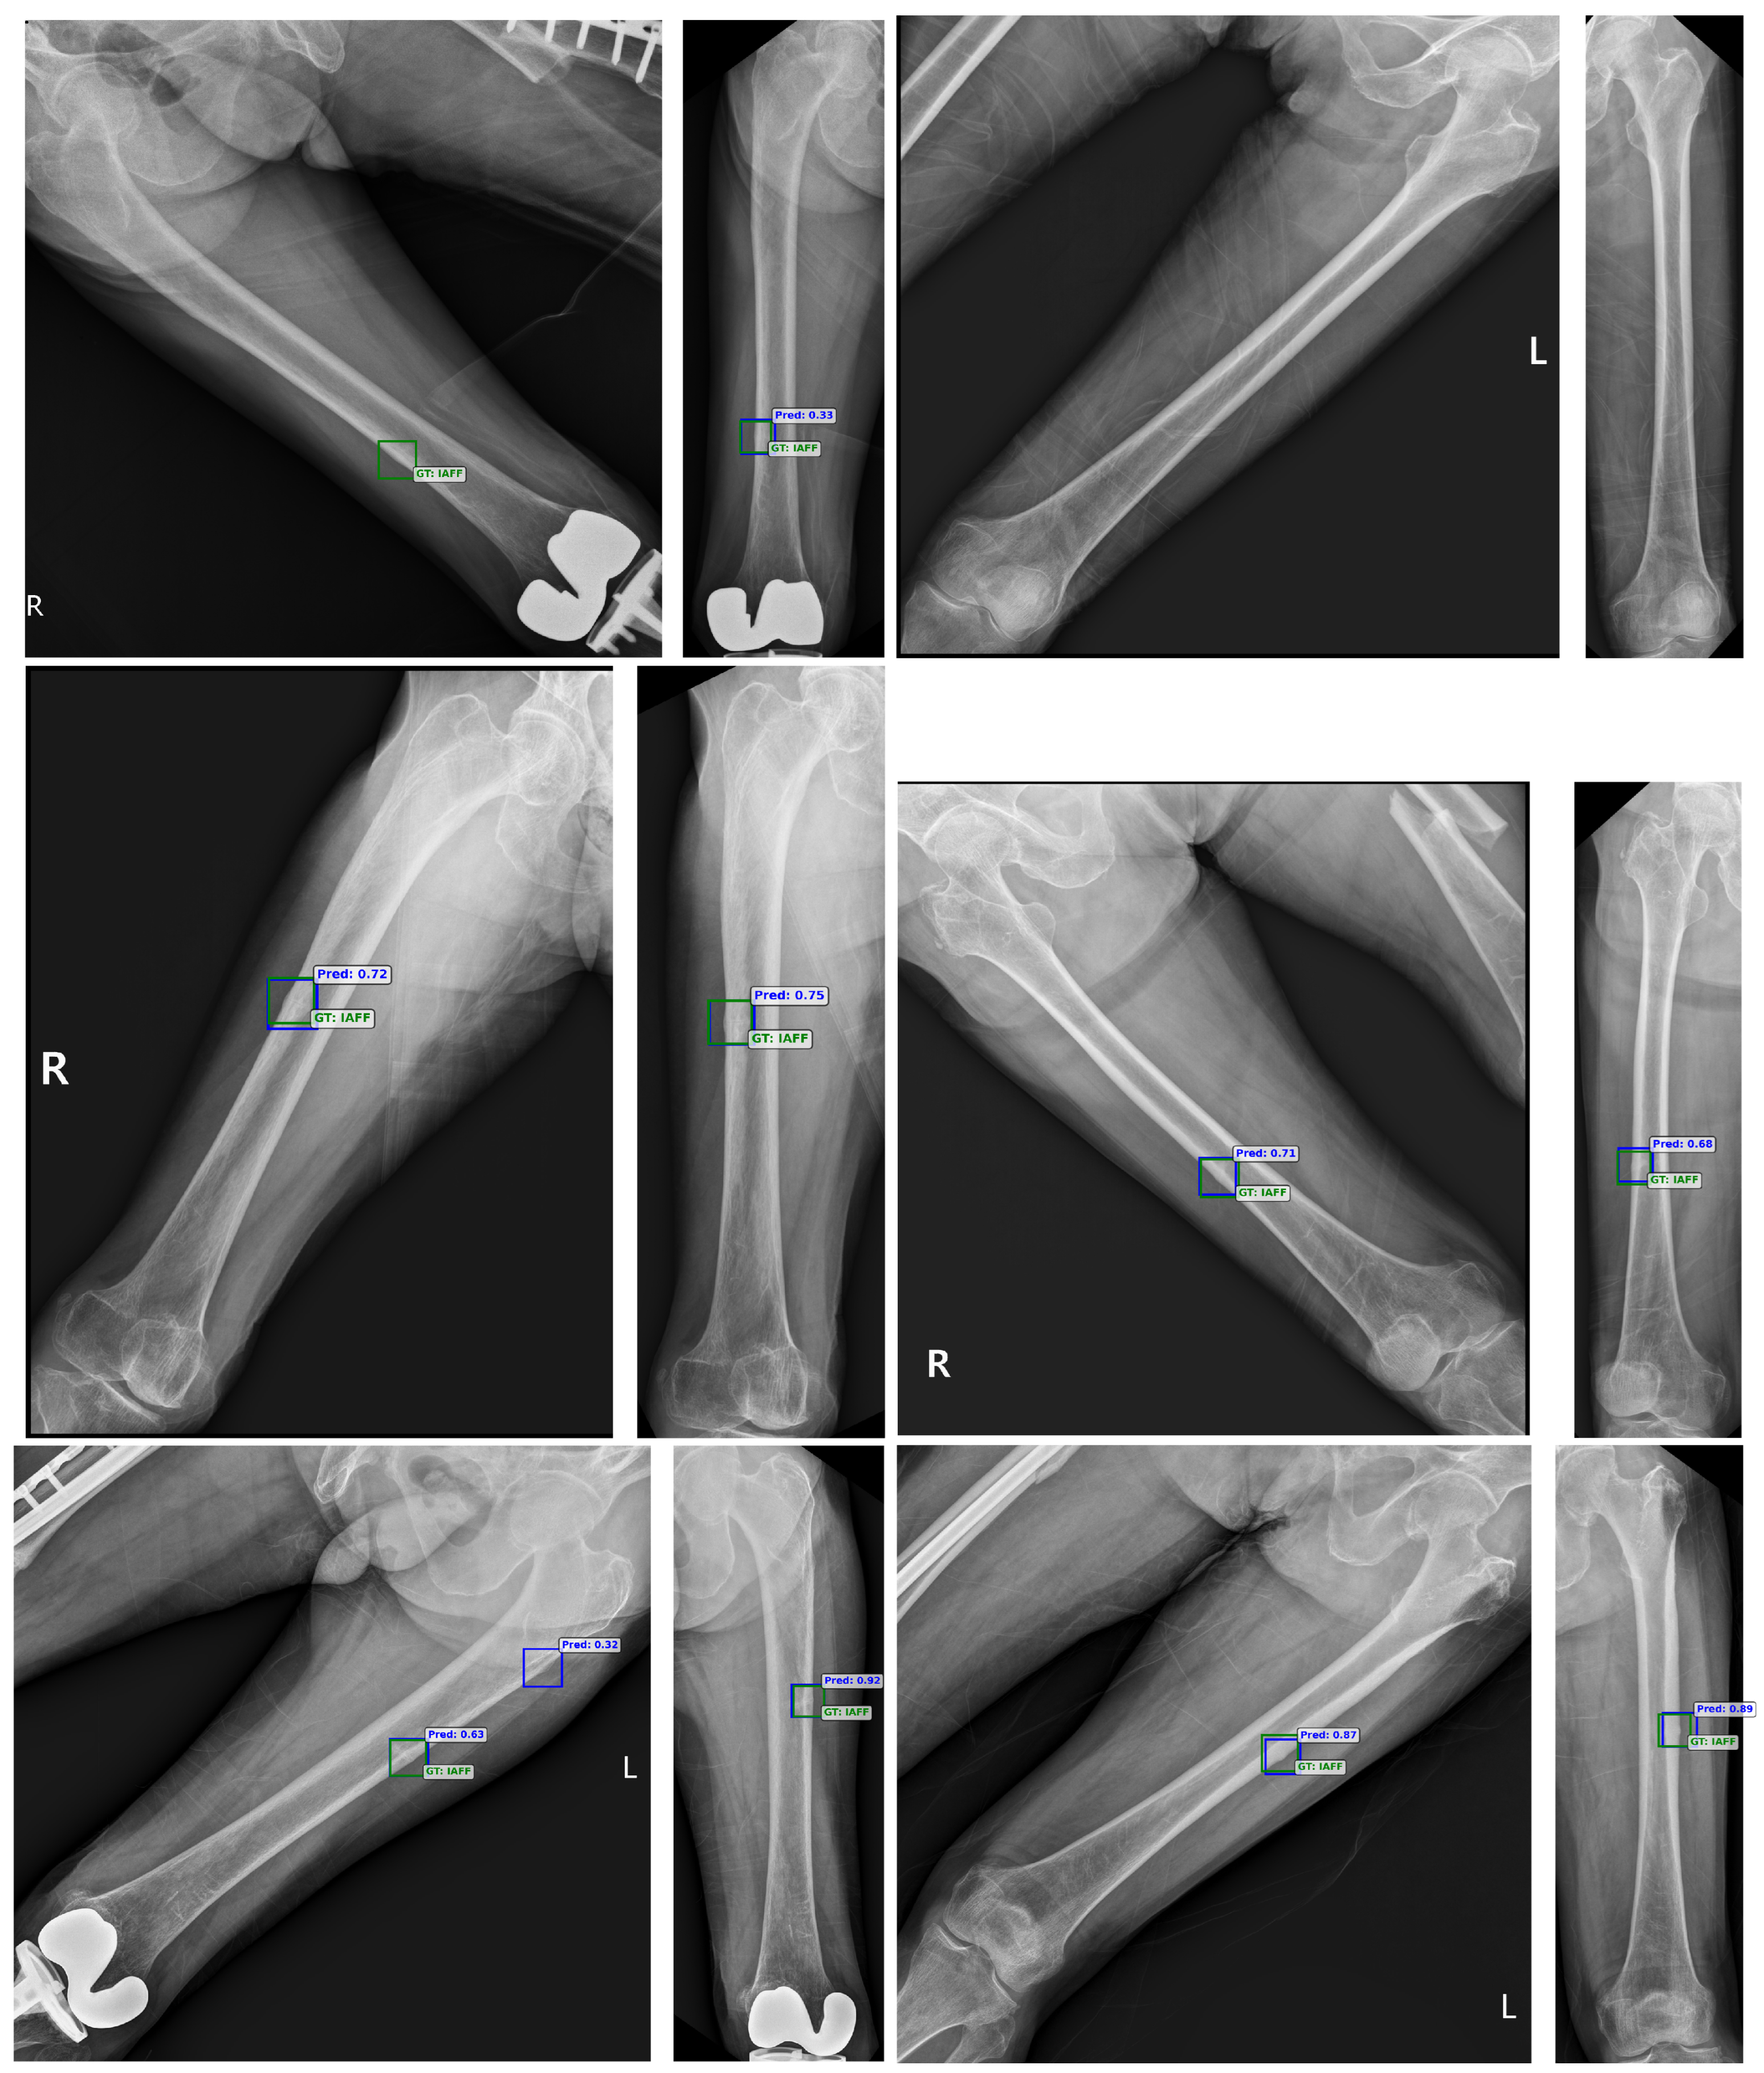

5.4. Visualization of Femoral and Alignment X-Ray

5.5. Error Analysis